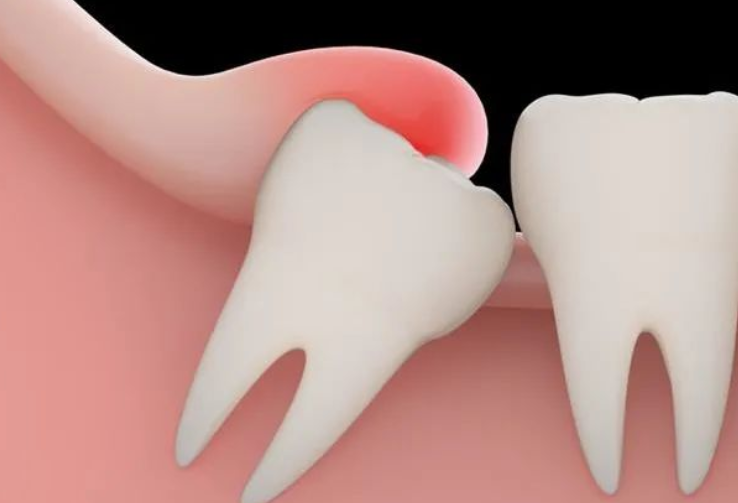

1、拔阻生智齒:拔智齒是這家醫(yī)院很不錯(cuò)的項(xiàng)目之一,醫(yī)生在做阻生和埋伏智齒拔除的時(shí)候,手法都比較細(xì)膩,形成的創(chuàng)口比較小,術(shù)后恢復(fù)的會(huì)比較快。

我的口腔當(dāng)中左側(cè)下面的智齒經(jīng)常會(huì)導(dǎo)致我牙齦疼痛,后來(lái)我才知道,這是因?yàn)檫@個(gè)牙齒有埋伏現(xiàn)象,為了能夠使這顆牙齒帶來(lái)的疼痛快點(diǎn)得到消除,我在南方醫(yī)科大學(xué)珠江醫(yī)院的牙科做了拔智齒的手術(shù)。